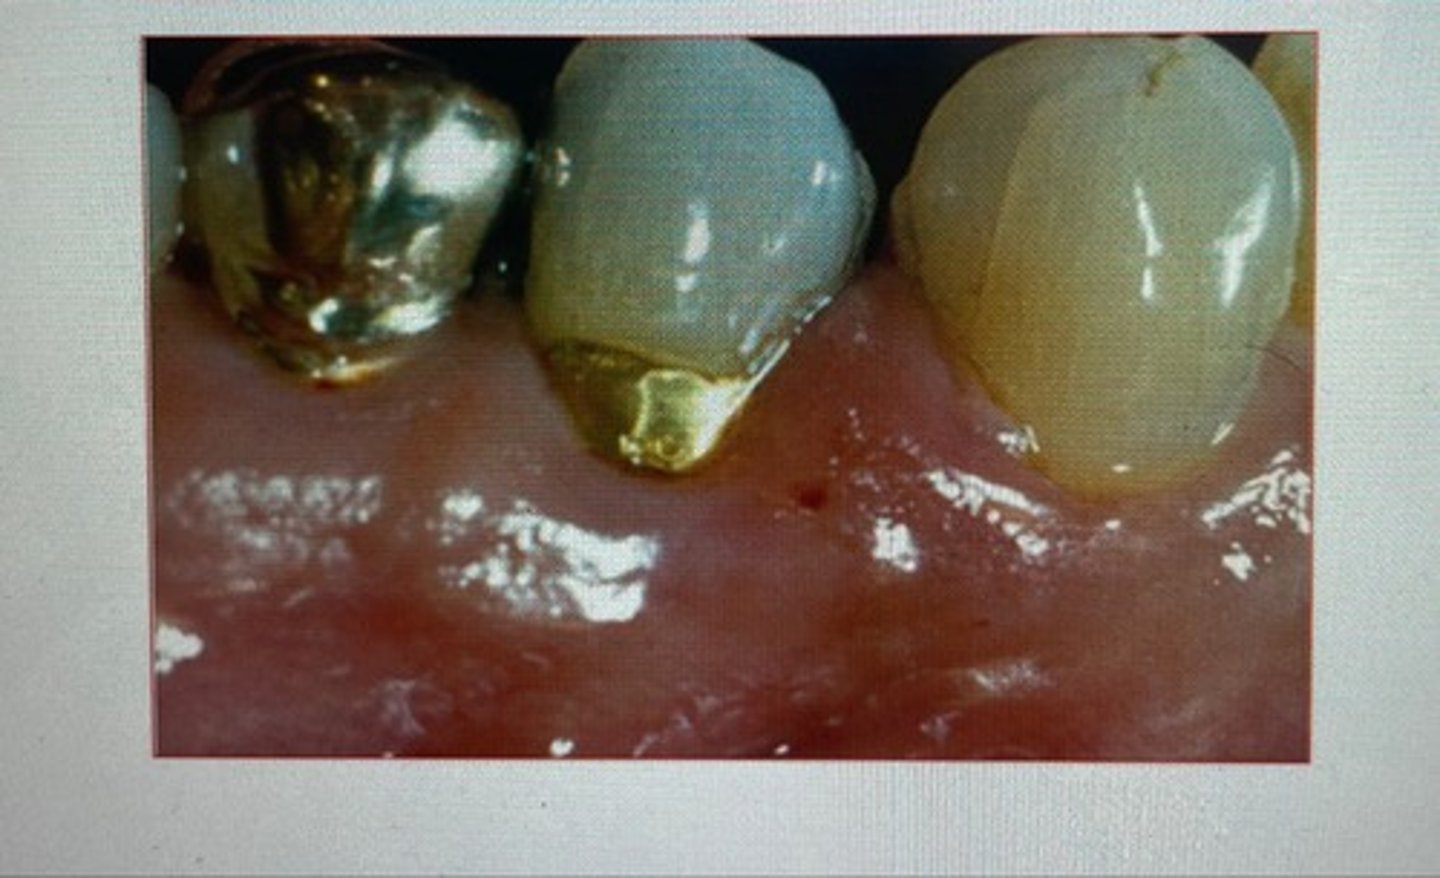

class II restoration